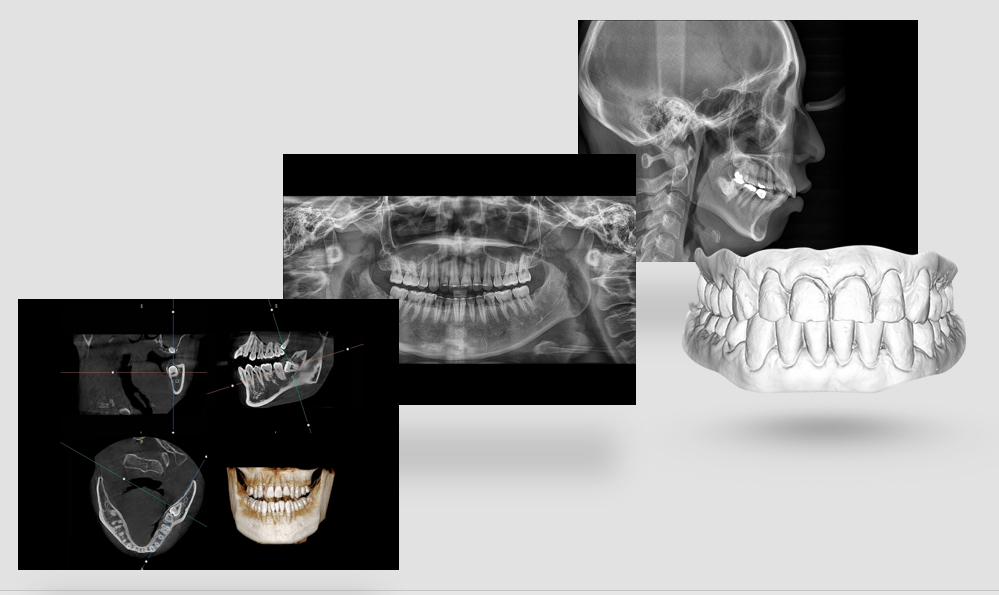

На выставке «Дентал Экспо Красноярск» успешно прошло заседание главных врачей во главе с Садовским Владимиром Викторовичем, Вице-президентом Общества Врачей России, Почетным Президентом СтАР, Директором Национального института исследований и адаптации маркетинговых стратегий (НИИАМС). Помимо насущных вопросов, руководители организаций региона обсудили преимущества и возможности использования стоматологического томографа Genoray Papaya 3D.

Несколько слов про преимущества:

- Уникальный моторизованный подбородочный упор с автоматическим позиционированием головы пациента в зависимости от типа и зоны исследования. Достаточно выбрать зону интереса. Все остальное делает сам аппарат!

18009043640e48e7b4e6074e6c36a5d1.png

- Плоскопанельный детектор имеет самую высокую в классе разрешающую способность

756273e2623420e0e796d77f551404ab.png